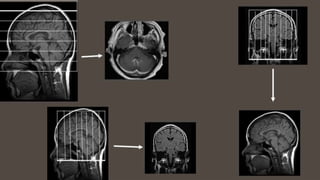

A plane passes through the

anatomical position.

It’s like slicing a loaf of bread. Instead of looking at the

or planes?

CORONAL

SAGITTAL

OBLIQUE

AXIAL

(TRANSVERSE)

plane

divides the

body into

right and

left

portions.

This is a

vertical

plane divides

the body into

front and

back or

anterior and

posterior

plane.

Axial plane

superior

and inferior

horizontal